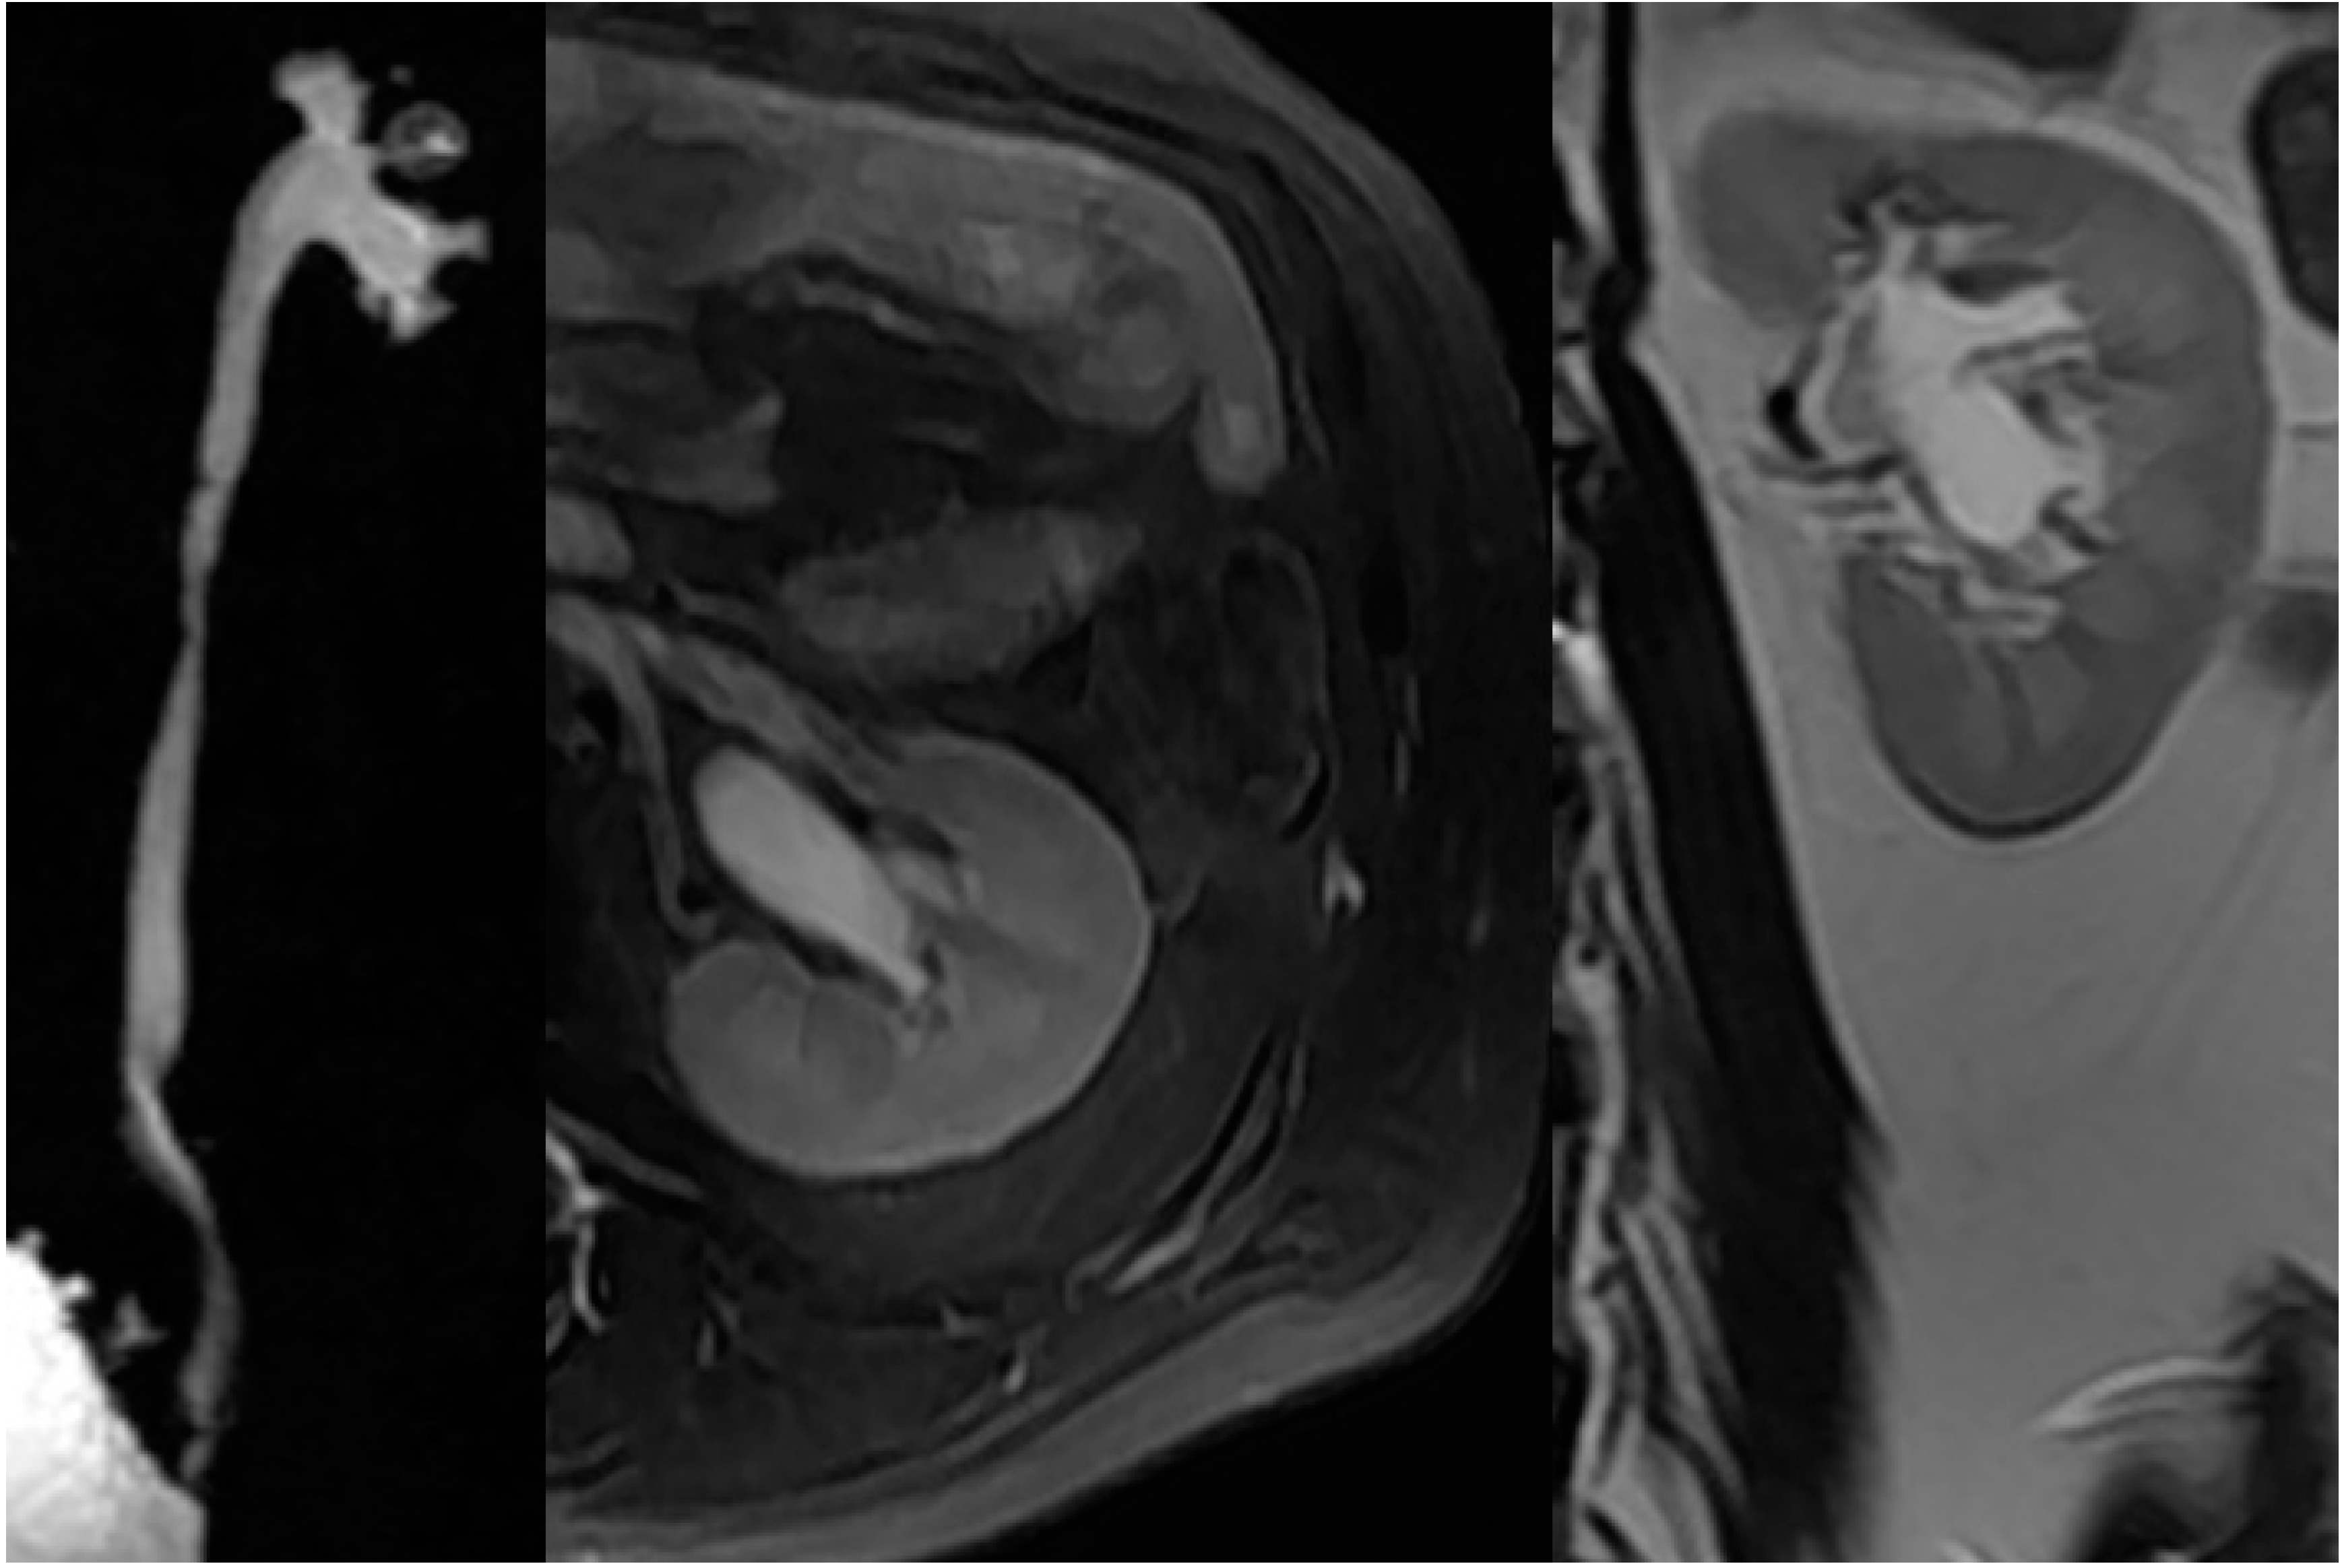

2.4. Upper Urinary Tract Imaging

2.4.1. Upper Urinary Tract Dilation (UUTD)

- Liao, L.M.; Zhang, F.; Chen, G. New grading system for upper urinary tract dilation using magnetic resonance urography in patients with neurogenic bladder. BMC Urol. 2014, 14, 38–45. [Google Scholar] [CrossRef] [PubMed]